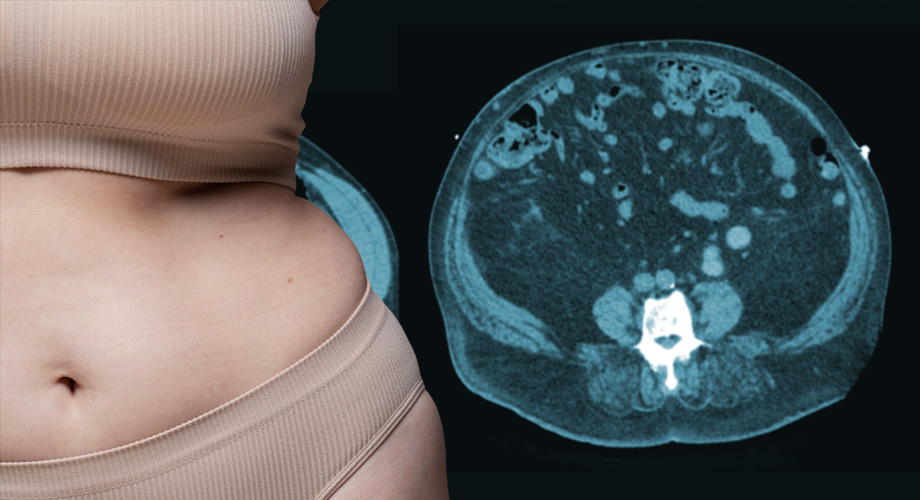

La grasa visceral, por otro lado, reside en lo profundo del abdomen, ubicada alrededor y dentro de órganos como el hígado, los intestinos y el páncreas. Esta ubicación aparentemente inofensiva (ya que no es aparente a simple vista) es precisamente lo que hace que la grasa visceral sea tan peligrosa.

A diferencia de su prima subcutánea, la grasa visceral es mucho más metabólicamente activa. Actúa como un órgano endocrino, produciendo hormonas y moléculas inflamatorias que pueden alterar el delicado equilibrio metabólico del cuerpo. Este tipo de grasa se relaciona más con la obesidad, aunque existen personas sin mucho sobrepeso, pero con niveles importantes de grasa visceral.

Es importante tener en cuenta que medir la distribución de la grasa corporal puede resultar complicado. Si bien la circunferencia de la cintura es un indicador simple, en entornos clínicos nutricionales se encuentran disponibles métodos más precisos, como exploraciones por tomografía (CT), resonancia magnética (MRI) o DEXA.